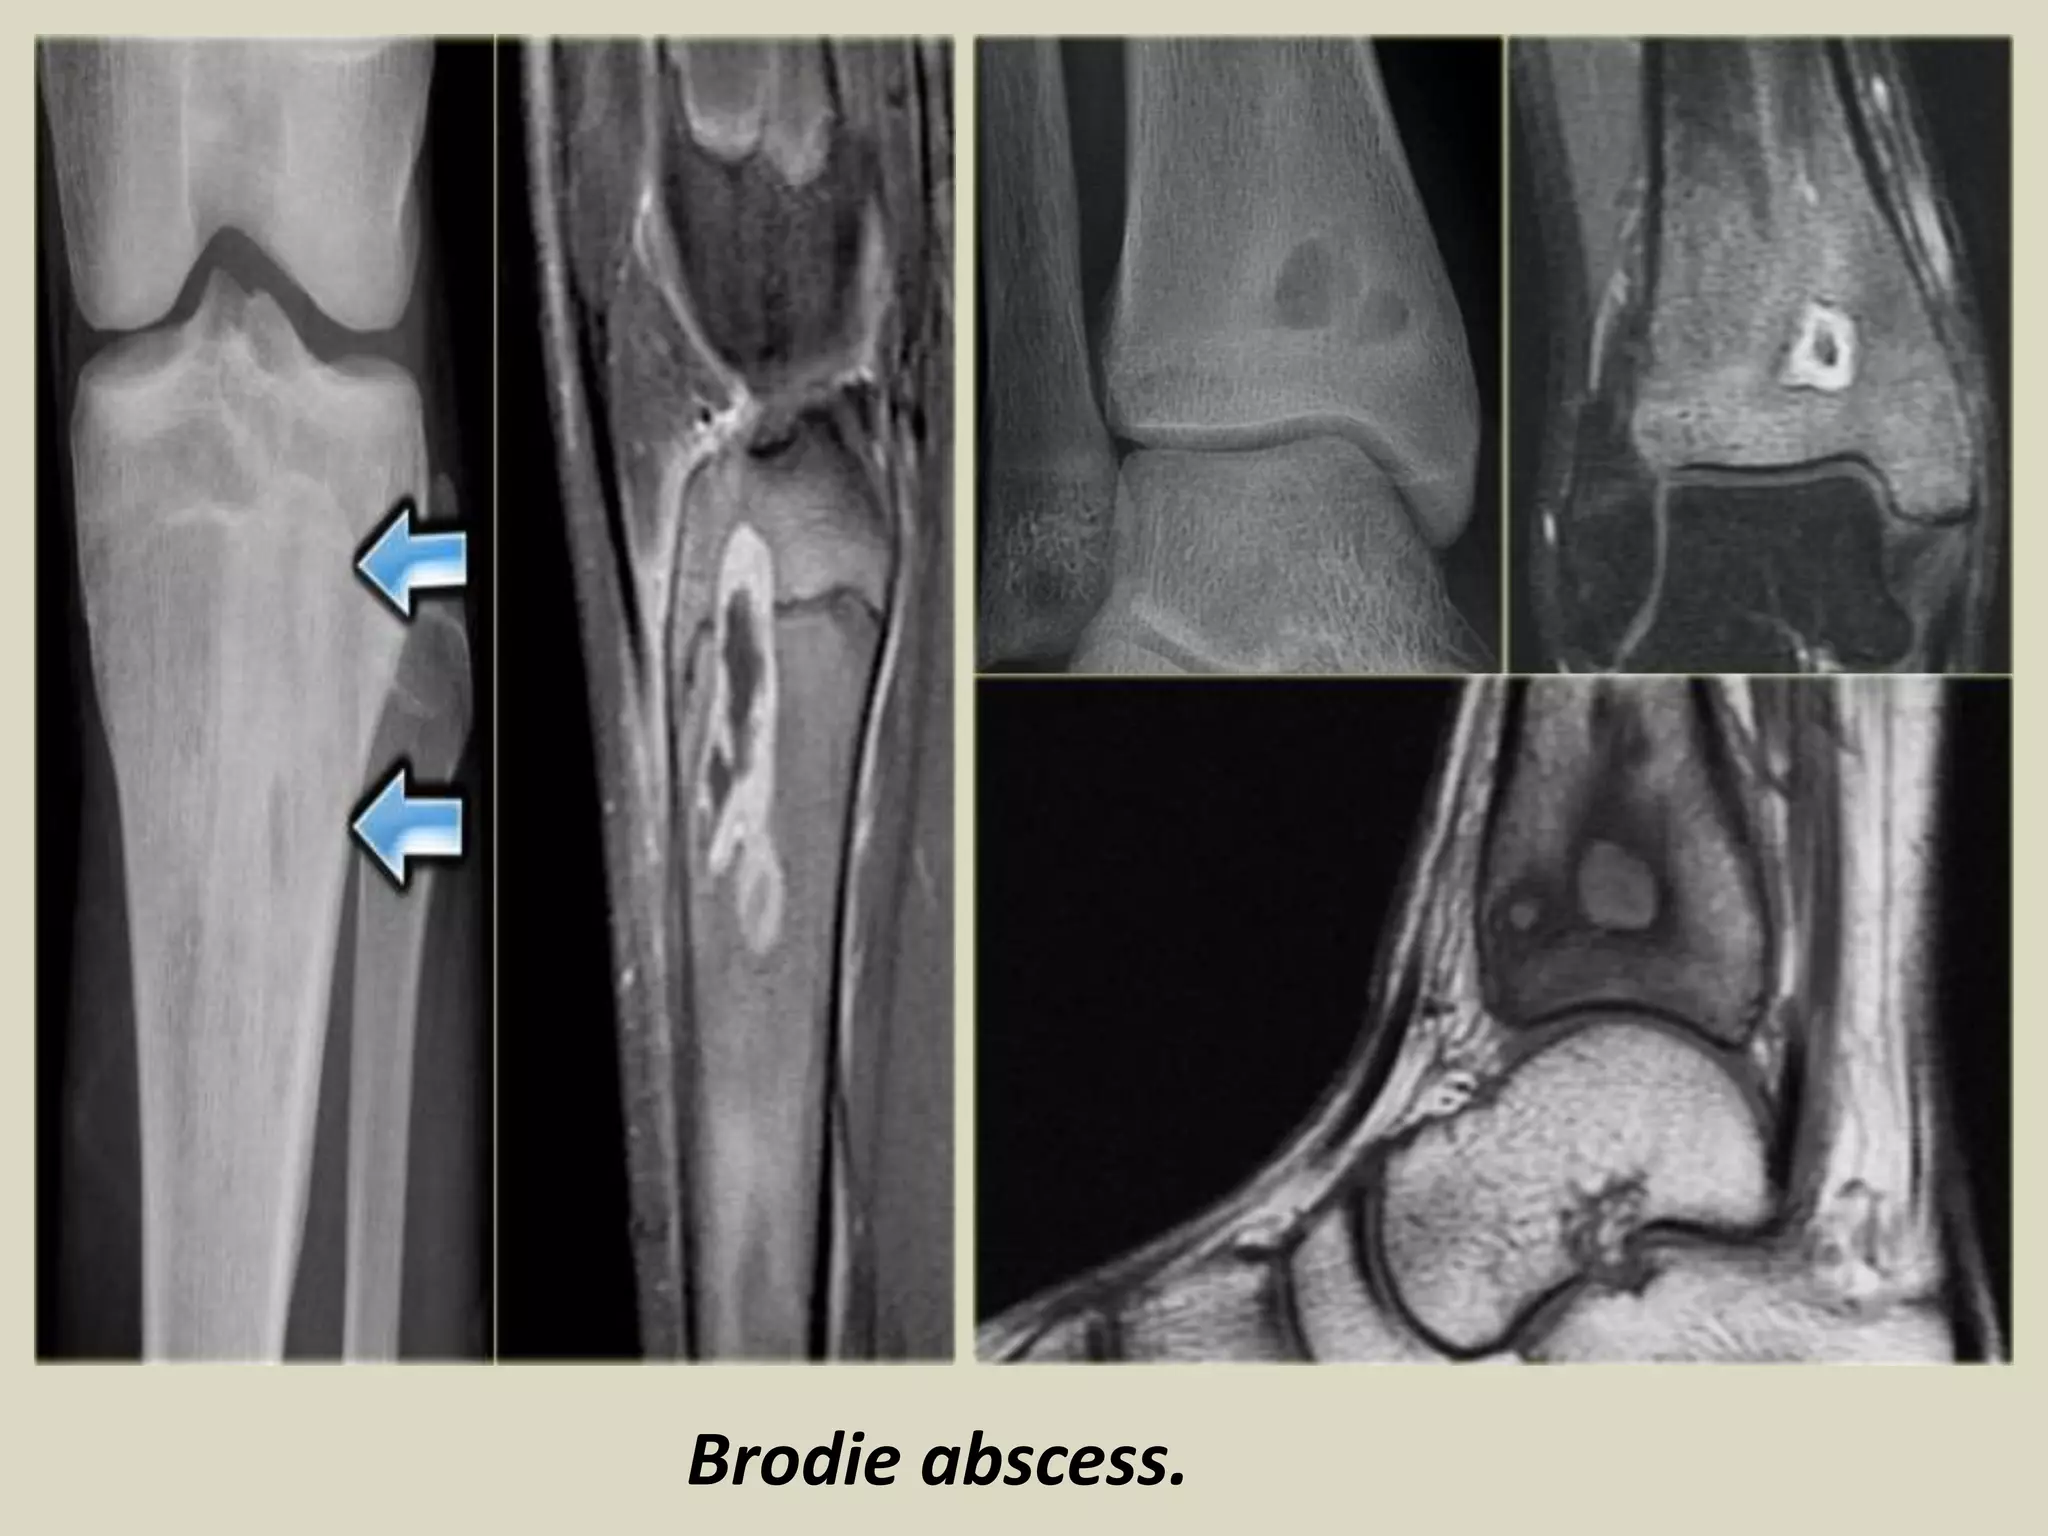

Brodie abscess – small intraosseous abscess that frequently involves the cortex

and is walled of by reactive bone. It may mimic tumor.

Brodie abscess.